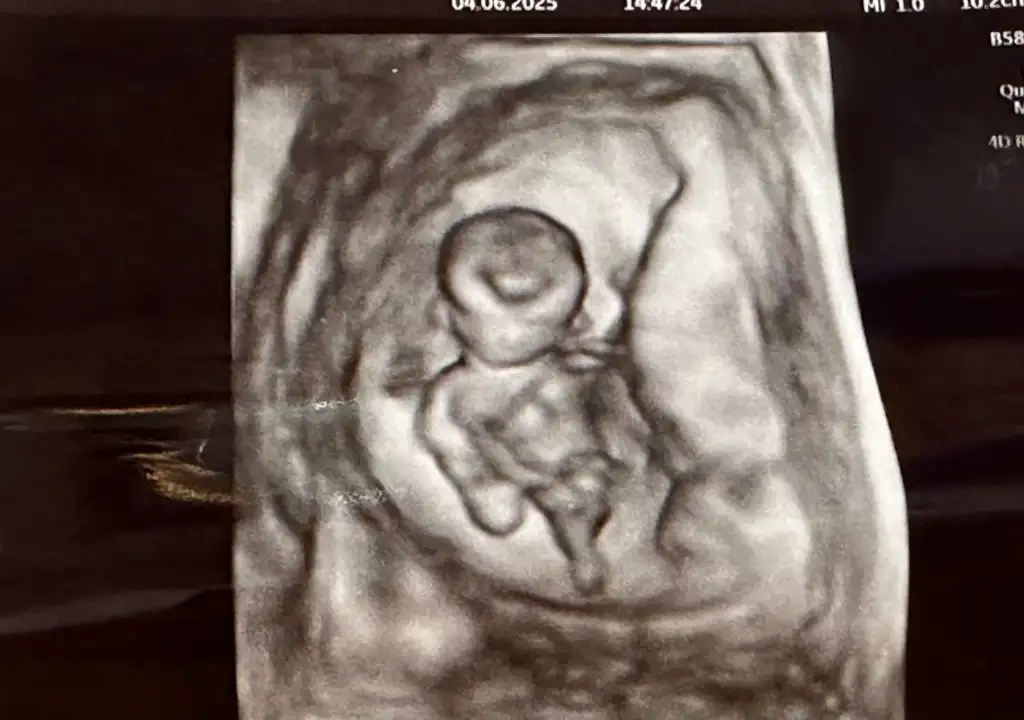

Bende merak ediyorum tahmini olan var mı ☺️

65,2 KB · Görüntüleme: 123

80,8 KB · Görüntüleme: 84